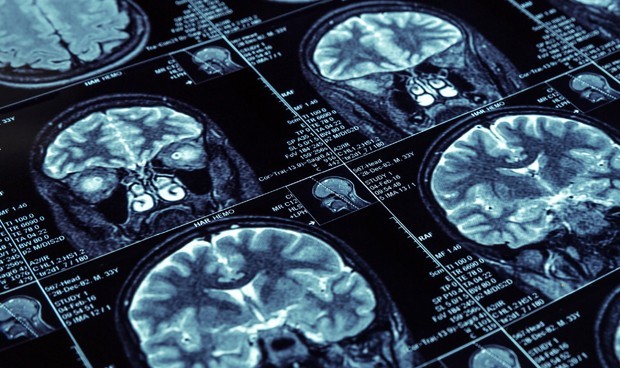

Efectos del SARS-CoV-2 en el SNC

Varias infecciones virales pueden causar daños importantes a la estructura y función del SNC y dar lugar a la aparición de encefalitis, encefalopatías tóxicas o lesiones desmielinizantes. Esto se ha explicado anteriormente en parte por la capacidad de estos virus de "invadir" el SNC, potencialmente dañando la barrera hematoencefálica, provocando daño nervioso directo y activando microglia y astrocitos en el cerebro y conduciendo a un efecto proinflamatorio Estado a nivel central.

Se han detectado transcripciones de ARN del SARS-CoV-2 en una pequeña cantidad de tejidos cerebrales humanos a partir de estudios recientes de autopsias, lo que respalda la idea de que este virus podría afectar el SNC y el tejido cerebral.

Estudios recientes han proporcionado pruebas de la capacidad neuroinvasiva del SARS-CoV-2 e identificado características patológicas con infiltrados mínimos de células inmunitarias.